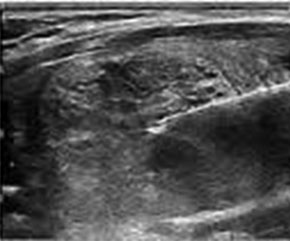

In cadrul acestei metode, un ac foarte subtire este intodus in glanda tiroida, sub ghidaj ecografic, pana la nivelul zonei ecografic suspecte (nodul sau chist), aspirandu-se de la nivelul nodulului suspect o cantitate foarte mica de celule sau lichid, care ulterior urmeaza a fi analizate si examinate citologic (la microscop) de catre medicului anatomo-patolog/citolog.

Punctia-aspiratie pe ac fin este indicata in cazul tuturor nodulilor mai mari sau egali cu 10 mm, cu caracteristice ecografice suspecte. Dintre acestea amintim cateva: nodul hipoecogen sau unic, nodul solid, margini neregulate, circulatie intranodulara haotica, microcalcificari, adenopatia patologica.

Linia ghid a Societatii Americane de Endocrinologie recomanda a se efectua punctia aspiratie pe ac fin pentru toti nodulii accesibili ecografic si cu caracteristici suspecte, nu doar pentru cei alesi pe criterii dimensionale (peste 10 mm).

FNA se indica si la noduli mai mici de 10 mm, daca au cel putin 2 caracteristici suspecte sau exista factori de risc.